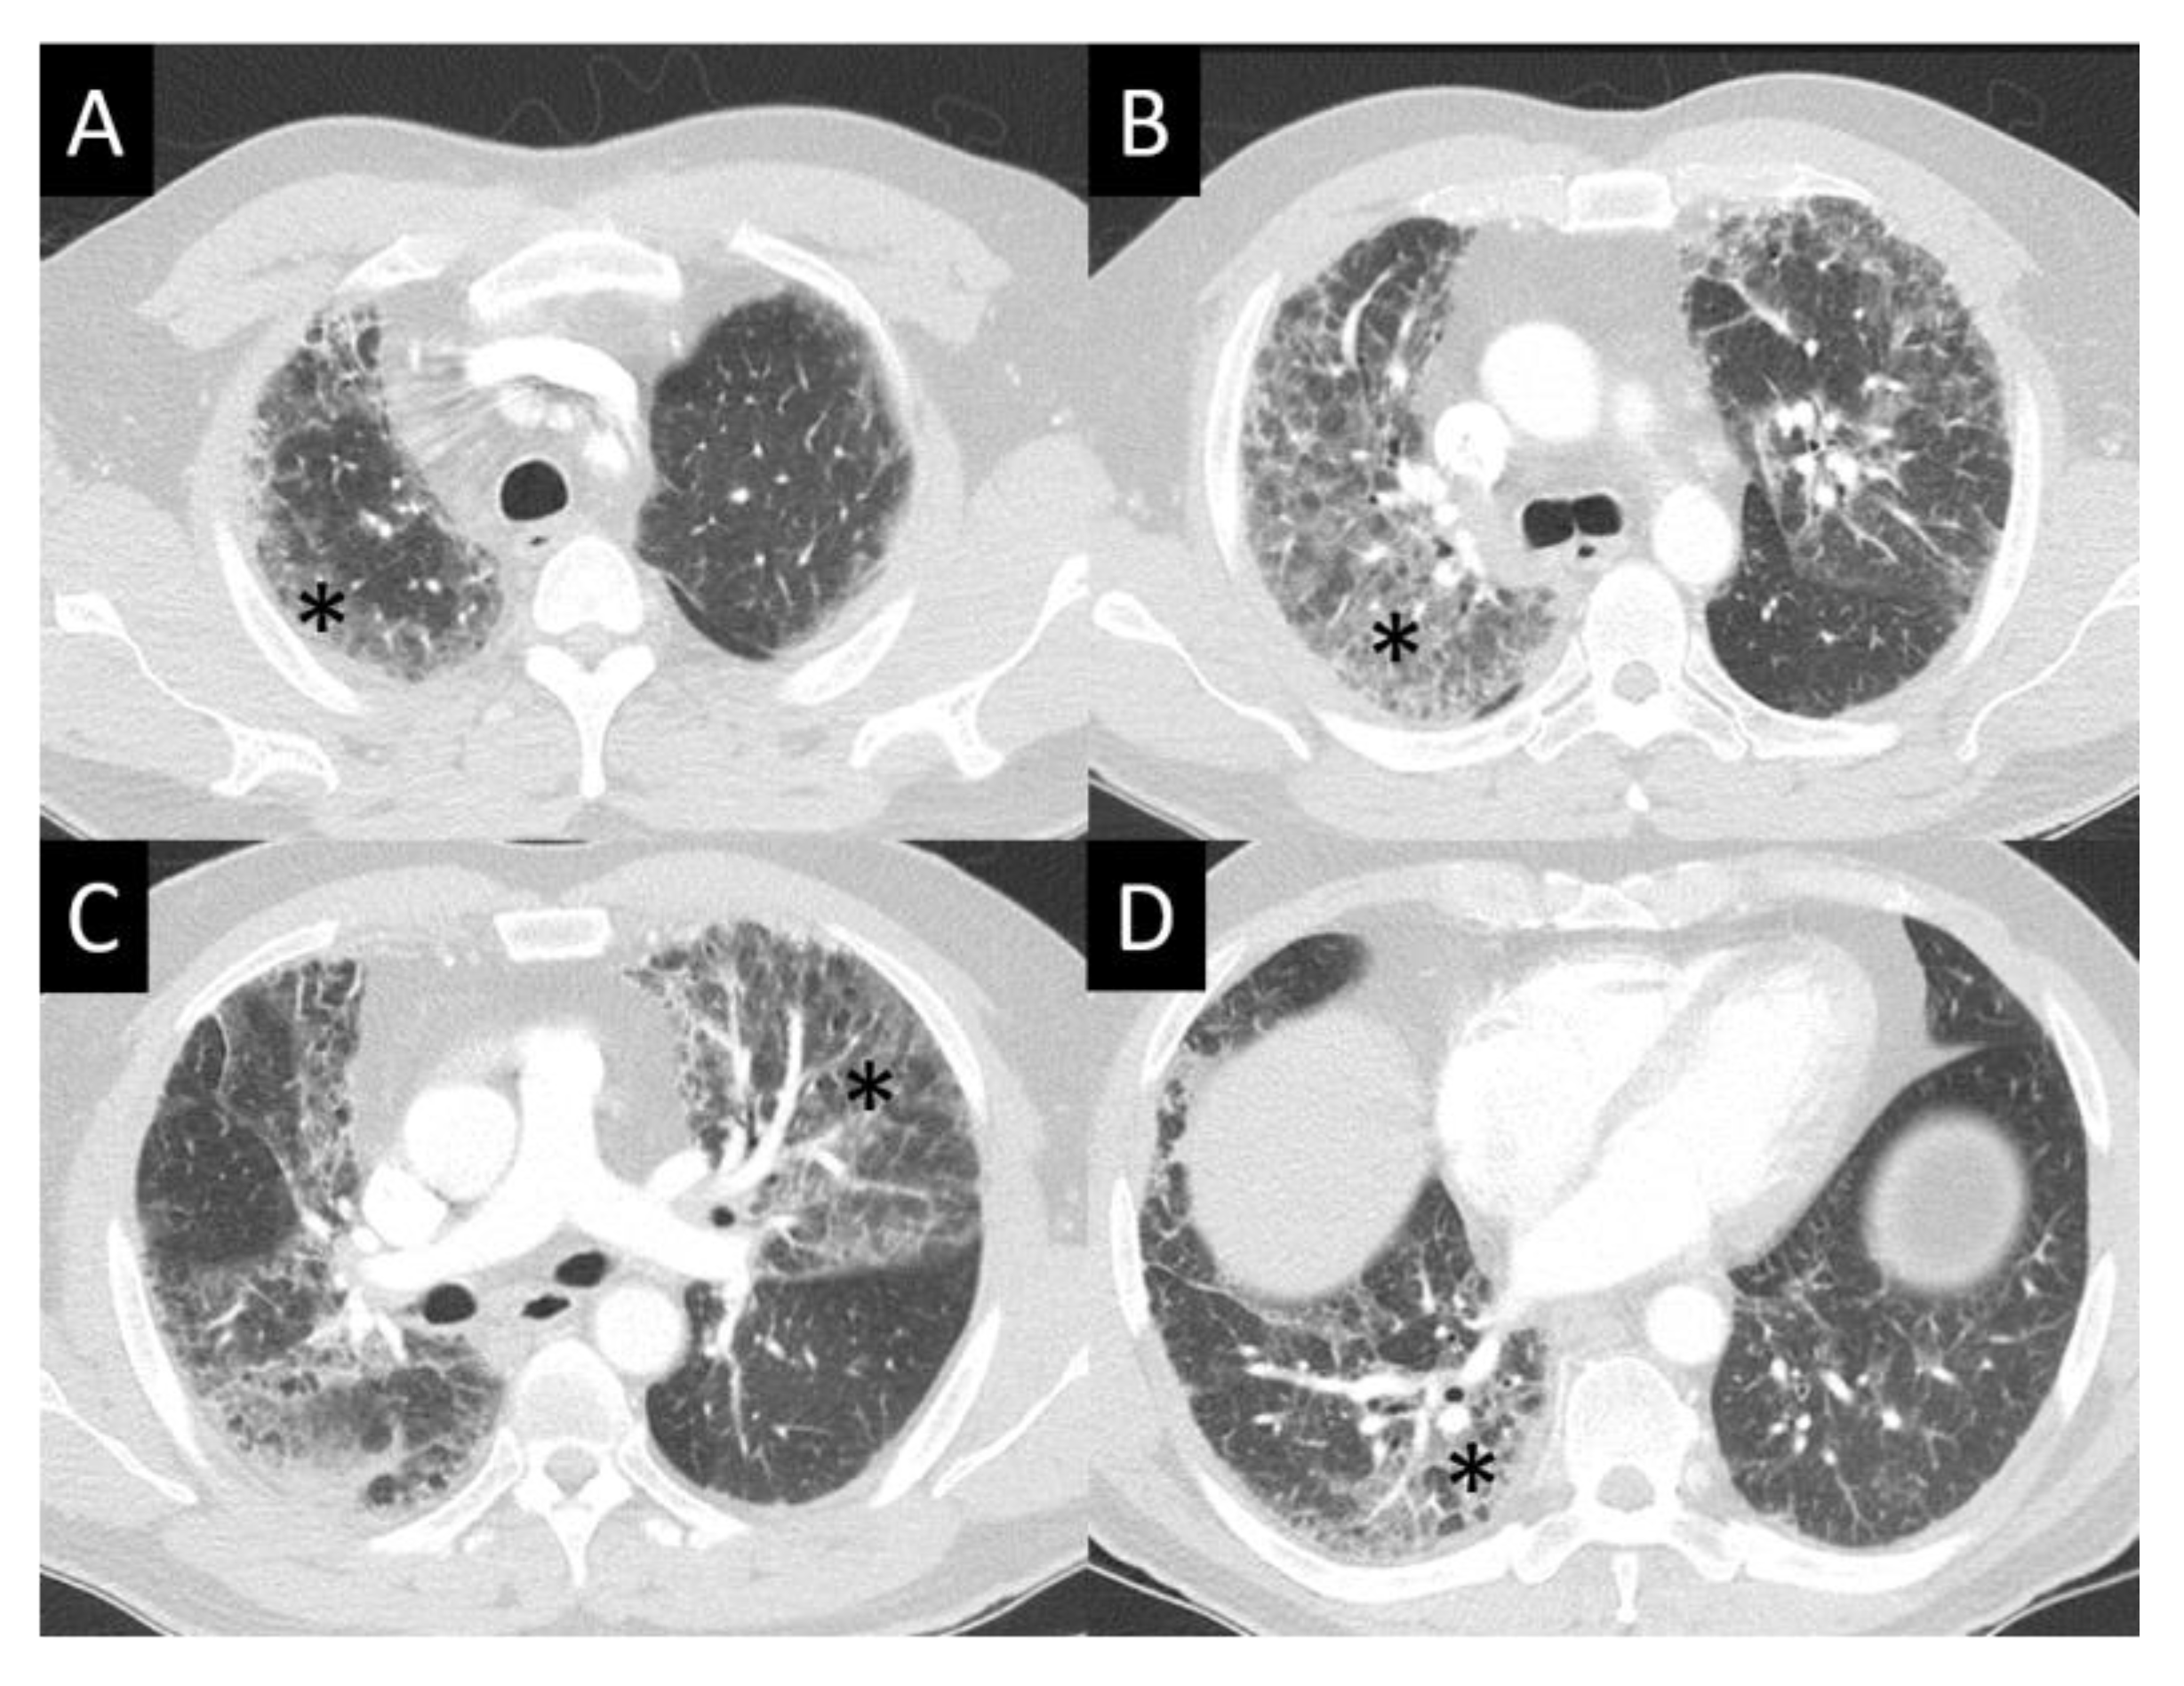

6.1.4. Chest Imaging

- Johkoh, T.; Lee, K.S.; Nishino, M.; Travis, W.D.; Ryu, J.H.; Lee, H.Y.; Ryerson, C.J.; Franquet, T.; Bankier, A.A.; Brown, K.K.; et al. Chest CT diagnosis and clinical management of drug-related pneumonitis in patients receiving molecular targeting agents and immune checkpoint inhibitors: A position paper from the Fleischner Society. Chest 2021, 159, 1107–1125. [Google Scholar] [CrossRef] [PubMed]